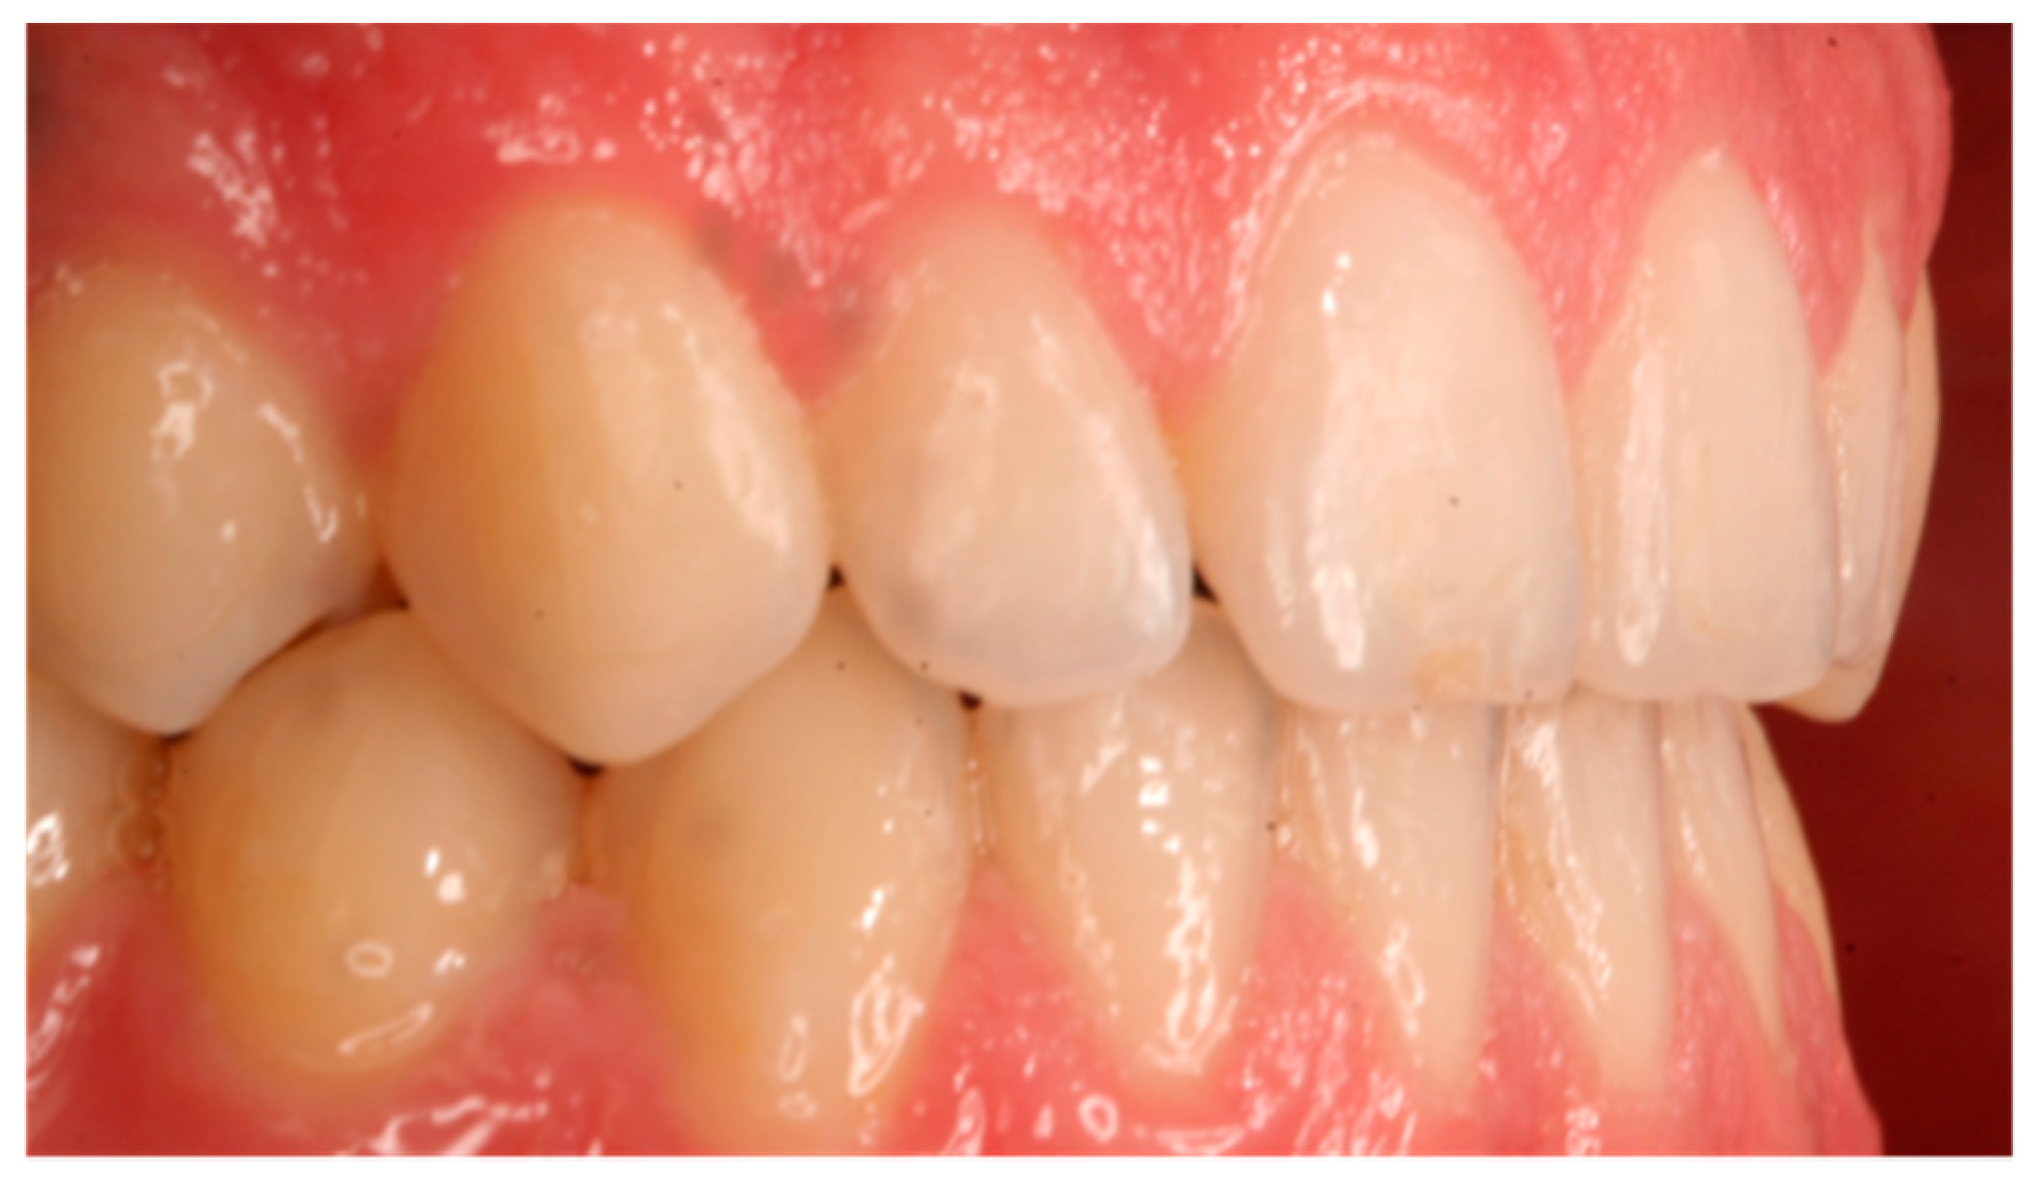

| Gingival Recessions | 1 | 1.72 |